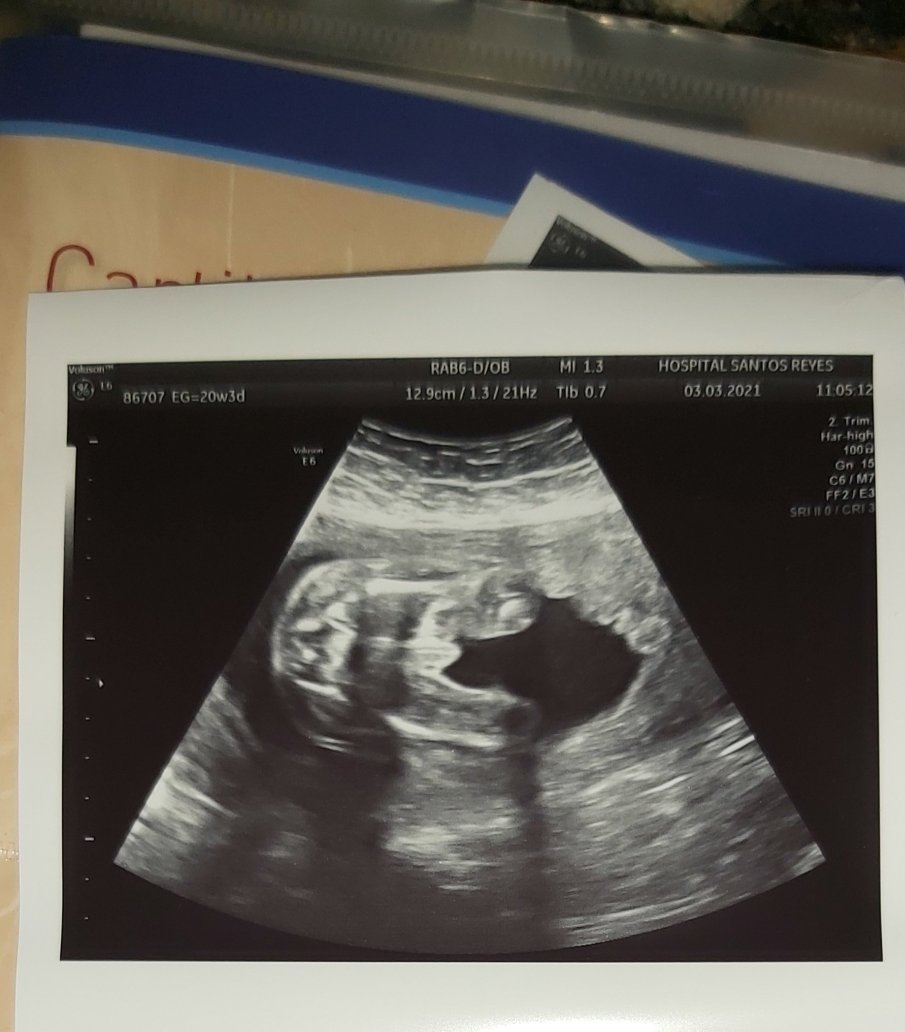

Какви са препоръчителните срокове за фетална морфология и дали е проблематично да се извърши по-рано от очакваното?

Феталната морфология обикновено се извършва между 19 и 22 седмица, но може да се направи и по-рано. В случай на предстоящ преглед на 19 + 6 г.с., важно е да имате предвид, че бебето обикновено се развива с около два дни напред, което може да доведе до по-точни резултати. Препоръчително е да се консултирате с вашия лекар относно всякакви промени в графика за прегледи, за да сте сигурни, че всичко е в норма.